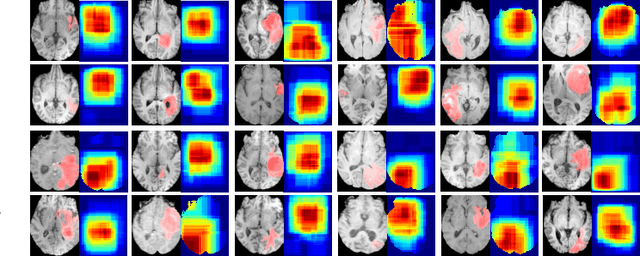

Abstract:Deep convolutional neural networks (CNNs) have been widely used for medical image segmentation. In most studies, only the output layer is exploited to compute the final segmentation results and the hidden representations of the deep learned features have not been well understood. In this paper, we propose a prototype segmentation (ProtoSeg) method to compute a binary segmentation map based on deep features. We measure the segmentation abilities of the features by computing the Dice between the feature segmentation map and ground-truth, named as the segmentation ability score (SA score for short). The corresponding SA score can quantify the segmentation abilities of deep features in different layers and units to understand the deep neural networks for segmentation. In addition, our method can provide a mean SA score which can give a performance estimation of the output on the test images without ground-truth. Finally, we use the proposed ProtoSeg method to compute the segmentation map directly on input images to further understand the segmentation ability of each input image. Results are presented on segmenting tumors in brain MRI, lesions in skin images, COVID-related abnormality in CT images, prostate segmentation in abdominal MRI, and pancreatic mass segmentation in CT images. Our method can provide new insights for interpreting and explainable AI systems for medical image segmentation. Our code is available on: \url{https://github.com/shengfly/ProtoSeg}.